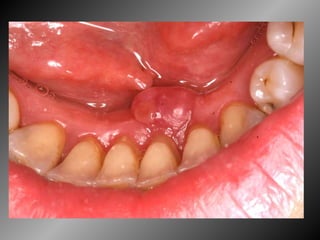

25 -  L.C.S., sexo masculino, 18 anos de idade, se apresentou com queixa de aumento de volume na gengiva entre os dentes 23  e  24.  Pelo  exame  clínico,  constatamos  a  presença  de  um  nódulo  séssil,  de  contornos  irregulares,  coloração  avermelhada, com sangramento abundante ao mínimo toque e evolução de 1 ano. O paciente apresentava higiene bucal precária com presença de placa bacteriana e tártaro. Com base no quadro clínico, o diagnóstico é: a) Fibroma e granuloma piogênico. b) Granuloma piogênico e hiperplasia fibrosa inflamatória. c) Lesão periférica (granuloma) de células gigantes e fibroma. d) Granuloma piogênico e lesão periférica (granuloma) de células gigantes. e) Hiperplasia fibrosa inflamatória e fibroma.

Granuloma Piogênico Lesão Nodular Séssil ou pediculada Avermelhada ou vinhosa Sangramento espontâneo e áreas de micro-ulceração superficial

Granuloma Piogênico Lesões nodulares de coloração avermelhada ou vinhosa Provavelmente uma reação inflamatória exagerada ao trauma menor Crescimento rápido, às vezes sangramento espontâneo Ocorre em qualquer idade mas parece mais freqüente em adultos jovens e adolescentes  Localização mais comum: gengiva (NEVILLE,2001)

Granuloma Piogênico Lesões mais antigas, são menos vasculares e mais fibrosas Papila interdental e regiões anteriores são áreas preferenciais, principalmente por vestibular (BORK,1996)

Granuloma Piogênico LesãoNodular Séssil ou pediculada Avermelhada ou vinhosa Sangramento espontâneo e áreas de micro-ulceração superficial

Granuloma Piogênico Lesõesnodulares de coloração avermelhada ou vinhosa Provavelmente uma reação inflamatória exagerada ao trauma menor Crescimento rápido, às vezes sangramento espontâneo Ocorre em qualquer idade mas parece mais freqüente em adultos jovens e adolescentes Localização mais comum: gengiva (NEVILLE,2001)

Granuloma Piogênico Lesõesmais antigas, são menos vasculares e mais fibrosas Papila interdental e regiões anteriores são áreas preferenciais, principalmente por vestibular (BORK,1996)